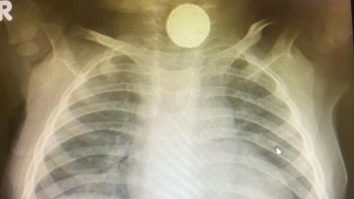

Un bebeluş din Marea Britanie a stat timp de 4 luni cu o baterie rotundă în gât. Medicii au crezut că are amigdalită

Government